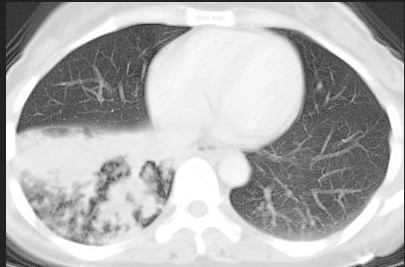

阻塞性肺炎的病因较多,比如肺结核、肿瘤等,各自有相应的体征及辅助检查结果。血常规可见白细胞升高。若影像学检查提示两上肺阻塞多以肺结核为主,两下肺阻塞则以肺部肿瘤为主。胸片等影像学中良恶性阻塞性肺炎的形态有时候非常相似,容易误诊,为了更好鉴别两种,要仔细询问病史,认真做好体格检查。必要时可以在B超或CT引导下肺肿块活检穿刺术或胸腔积液做生化、肿瘤标志物、组化免疫学和做细胞学、组织学等病理学确诊。